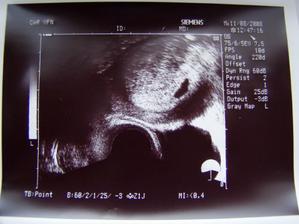

11.8. první kontrola ..to jsem zvedava ...Teksasatko je tam huraaa....dalsi kontrola